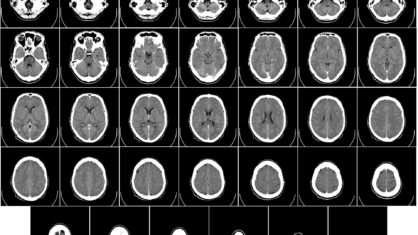

No estudo de Tufts, os pesquisadores procuraram vitamina D em quatro regiões do cérebro, duas delas ligadas à doença de Alzheimer, uma associada a formas de demência ligadas ao fluxo sanguíneo e uma região sem nenhuma associação conhecida com o Alzheimer. Os pesquisadores descobriram que a vitamina D estava realmente presente no tecido cerebral e altos níveis de vitamina D em todas as quatro regiões do cérebro se correlacionavam com uma melhor função cognitiva.